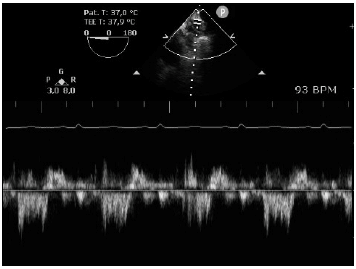

Analise a figura a seguir.

O achado demonstrado nesta imagem de Doppler da veia pulmonar é encontrado em